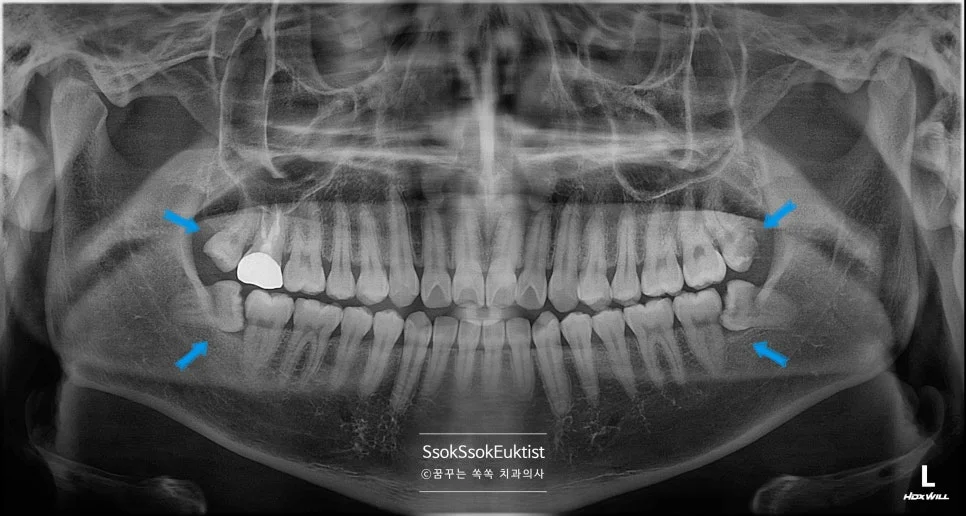

오른쪽 위 사랑니 발치 후 방사선

오른쪽 위 사랑니 발치 후 X-ray

오른쪽 아래 매복 사랑니 발치 후 방사선

오른쪽 아래 매복 사랑니 발치 후 X-ray

사랑니가 예쁘게 발치된 모습입니다^^

사랑니 4개 발치 완료 최종 파노라마

최종 파노라마 — 사랑니 4개 모두 발치 완료